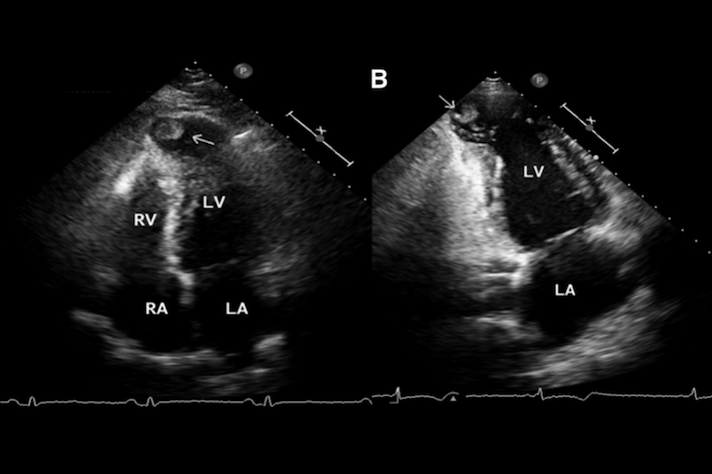

- Ecocardiograma

O ecocardiograma é uma exame que fornece imagens detalhadas do coração, permitindo a avaliação da estrutura e função cardíaca.